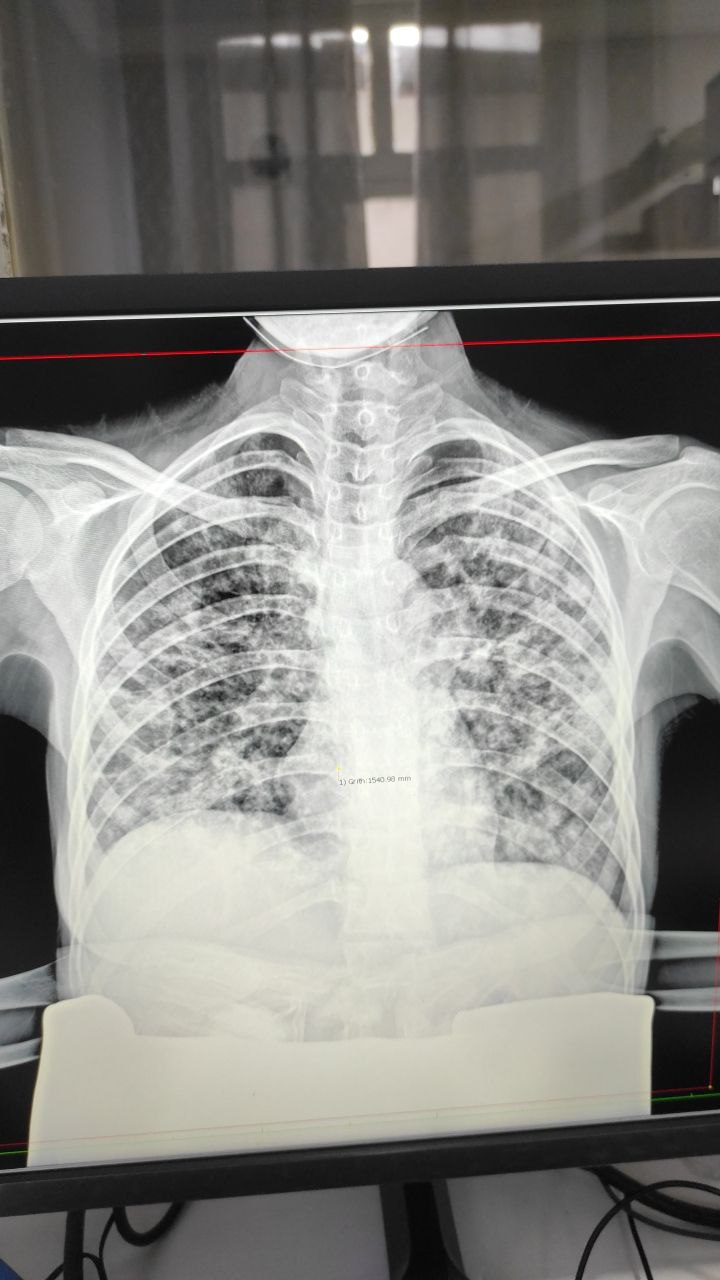

Релаксация купола? Киста? Н/о?

По моему на релаксации не похож

Там округлой тень

Tbs?

Женщина молодая 22 лет беременность 27 недель

Ковид?

С чего вдруг сразу ковид?

Это похоже на вирусную пневмонию, которые ну никак друг от друга не отличаются

Понятное дело, что с учётом эпидобстановки любая вирусная пневмония скорее всего окажется ковидом.

Но не надо уж сразу выставлять такой диагноз на основании лучевых исследований

Сатурация 97 %

Кашель более 4 месяца

Потеря аппетита

Озноб

Да на диссеминации подозревали и отправили к фтизиатру